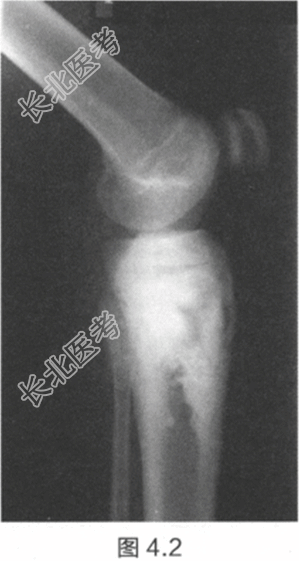

- [材料题] 一名15岁男孩,在度假做日光浴期间,父亲帮忙涂防晒霜时意外发现其小腿上端有肿块。肿块已经出现6个月,并且近期逐渐增大。检查:胫骨近端有一个坚硬、不规则、有压痛的肿块。肿块无疼痛,不影响膝关节活动,其他部位未见肿块。膝关节X线片见图4.1和图4.2。红细胞沉降率(ESR)和血清碱性磷酸酶升高。

- 简答题2、描述一下X线片特征。